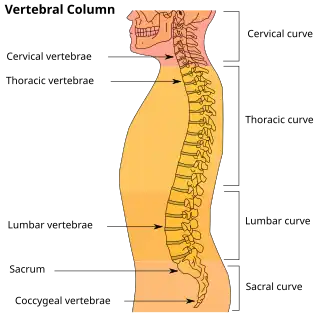

| Diagram showing normal curvature (posterior concavity) of the cervical (neck) and lumbar (lower back) vertebral column (spine) | |

Lordosis is historically defined as an abnormal inward curvature of the lumbar spine.[1][2] However, the terms lordosis and lordotic are also used to refer to the normal inward curvature of the lumbar and cervical regions of the human spine.[3][4] Similarly, kyphosis historically refers to abnormal convex curvature of the spine. The normal outward (convex) curvature in the thoracic and sacral regions is also termed kyphosis or kyphotic. The term comes from Greek lordos 'bent backward'.[5]

Lumbar hyperlordosis is excessive extension of the lumbar region, and is commonly called hollow back or saddle back (after a similar condition that affects some horses). Sway back is a different condition with a different cause, that at a glance can mimic the outward appearance of lumbar hyperlordosis. Lumbar kyphosis is an abnormally straight (or in severe cases flexed) lumbar region.

Normal lordotic curvatures, also known as secondary curvatures, result in a difference in the thickness between the front and back parts of the intervertebral disc. Lordosis may also increase at puberty, sometimes not becoming evident until the early or mid-20s.